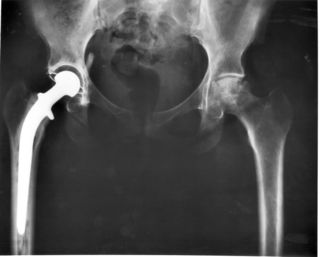

صورة بأشعة إكس، مفصل المريض (يسار الصورة) تم استبداله، with the ball of this ball-and-socket joint replaced by a metal head that is set in the thighbone or femur and the socket replaced by a white plastic cup (clear in this X-ray). Pelvic anatomy consistent with that of a female (large infrapubic angle, large pelvic opening). | |

استبدال مفصل الورك Hip replacemen، هي عملية جراحية يتم فيها استبدال مفصل الورك بمزورعة طبية صناعية. يمكن أن تجرى جراحة استبدال مفصل الورك كاستبدال تام أو نصفي. تهدف هذه الجراحة بشكل عام إلى إزالة ألم التهاب المفصل أو لإصلاح تخرب المفصل الفيزيائي كجزء من علاج كسر مفصل الورك. يتألف استبدال مفصل الورك التام (رأب مفصل الورك التام) من استبدال كل من الحق acetabulum ورأس الفخذ في حين يستبدل بشكل عام في تصنيع المفصل النصفي (رأب المفصل النصفي) رأس الفخذ فقط. تعتبر عملية استبدال مفصل الورك حالياًً عملية الجراحة العظمية الأكثر نجاحاً و موثوقيةً حيث أبدى 97% من المرضى تحسناً ملحوظاً.